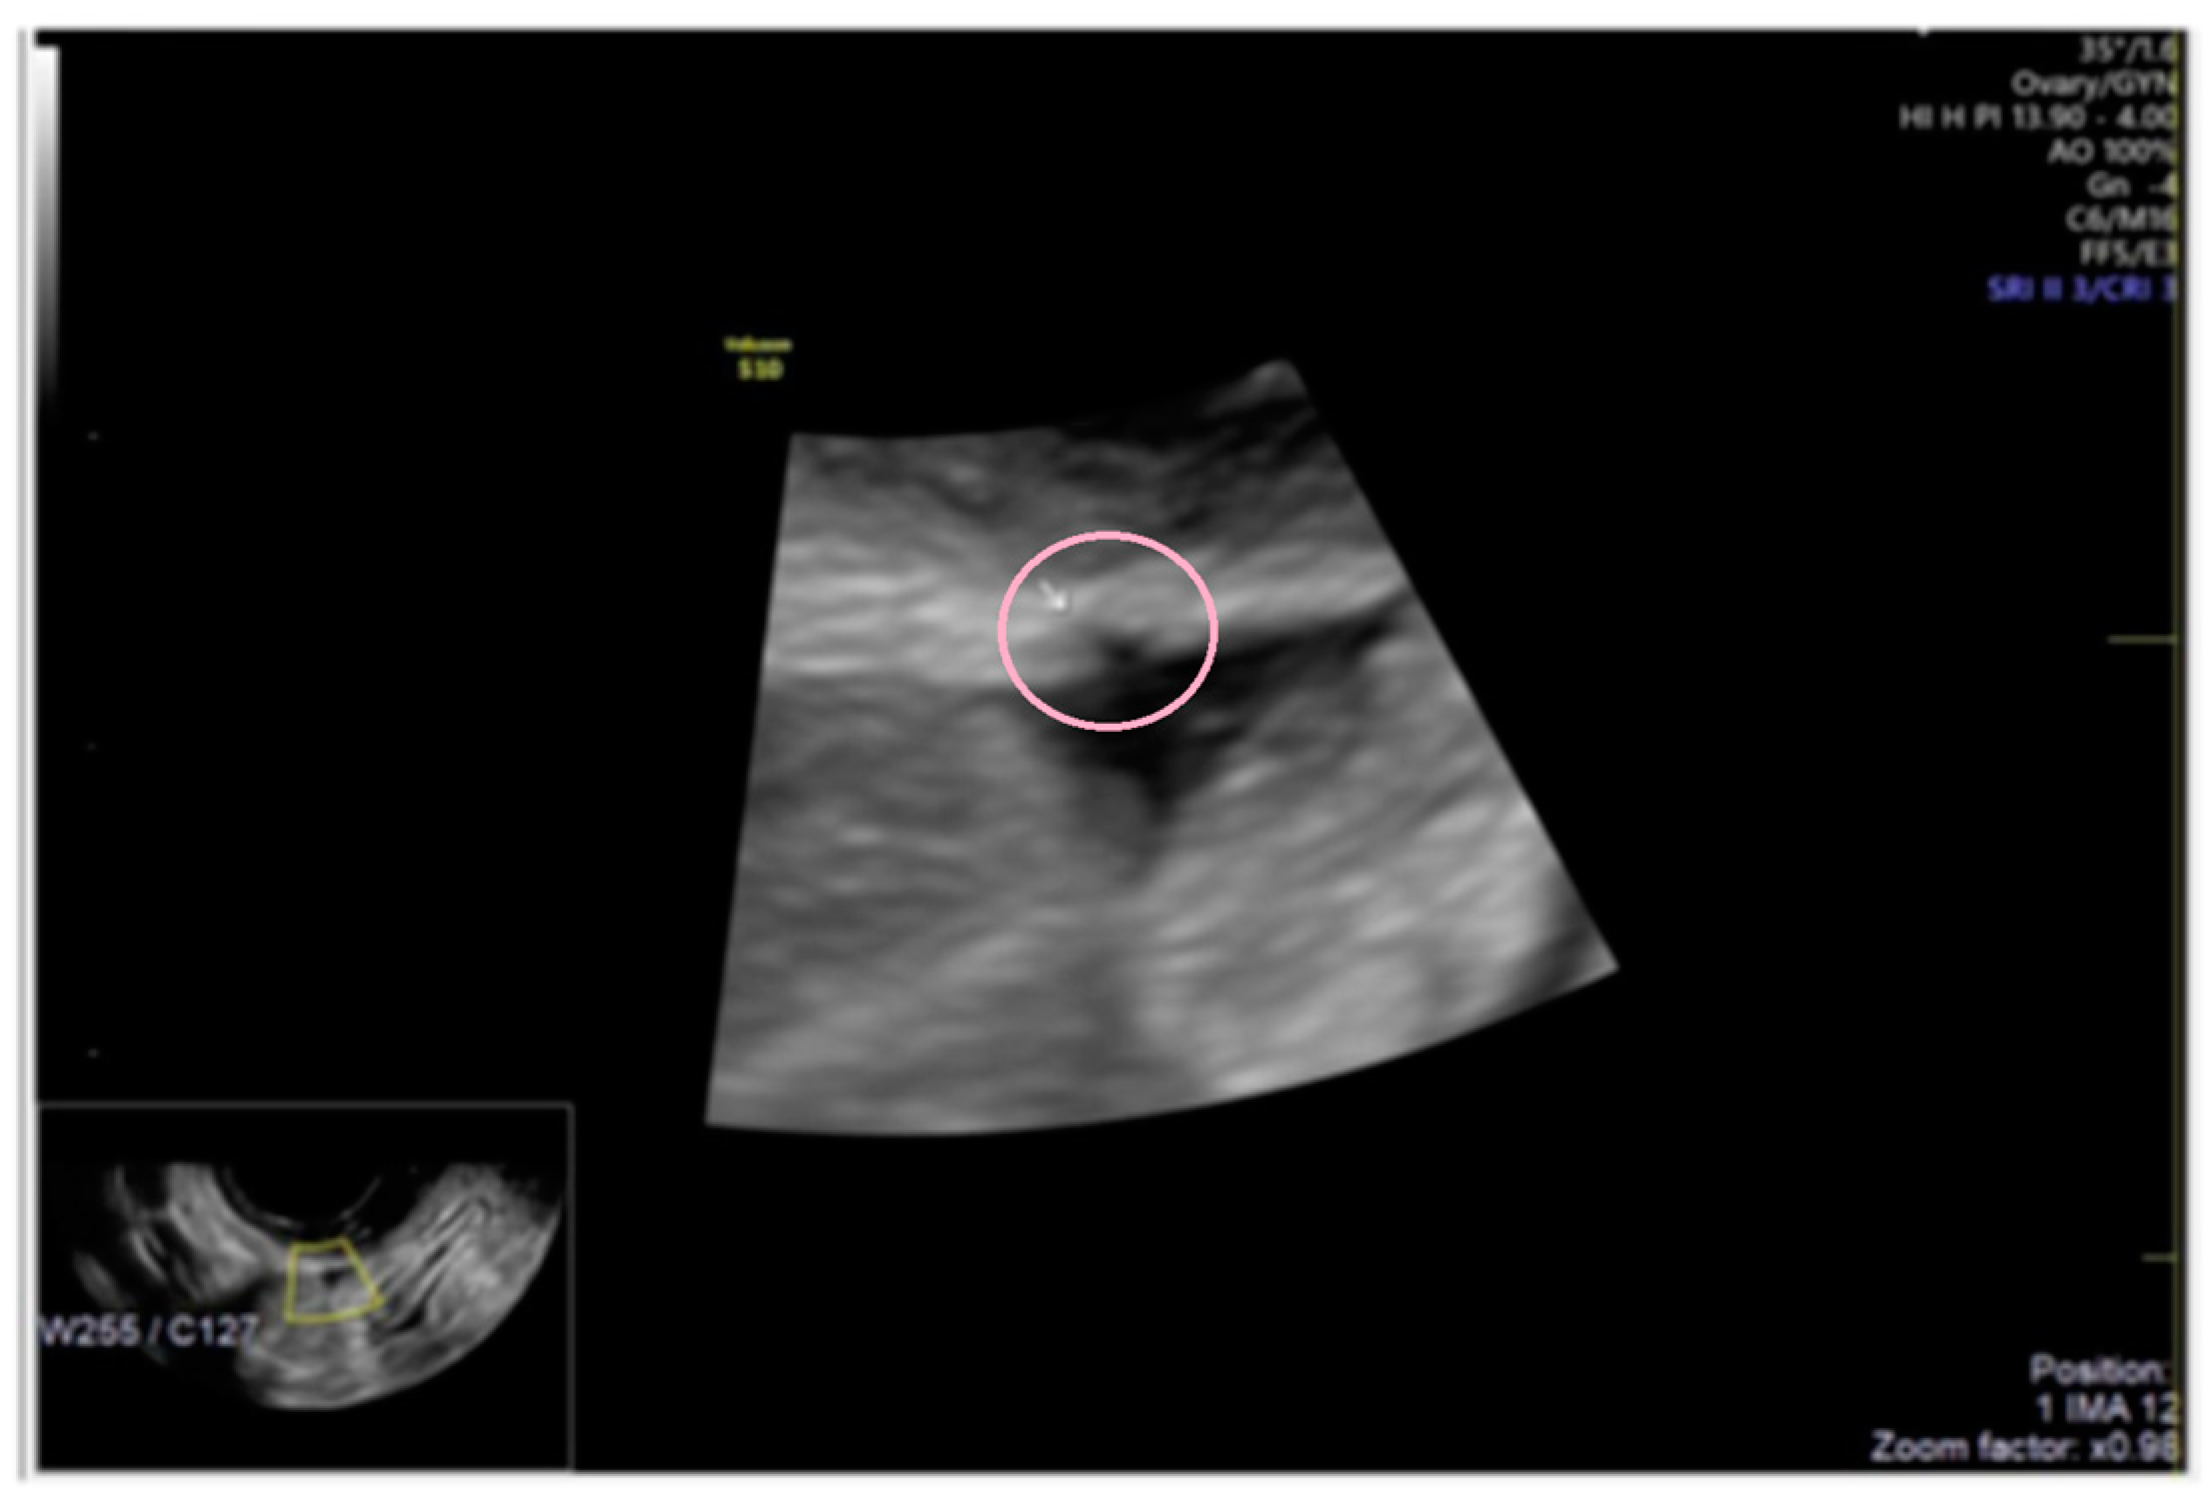

- The presence of hyperechoic foci (we called this a “pearl”).

3.1. Cystic Solitary Lesion